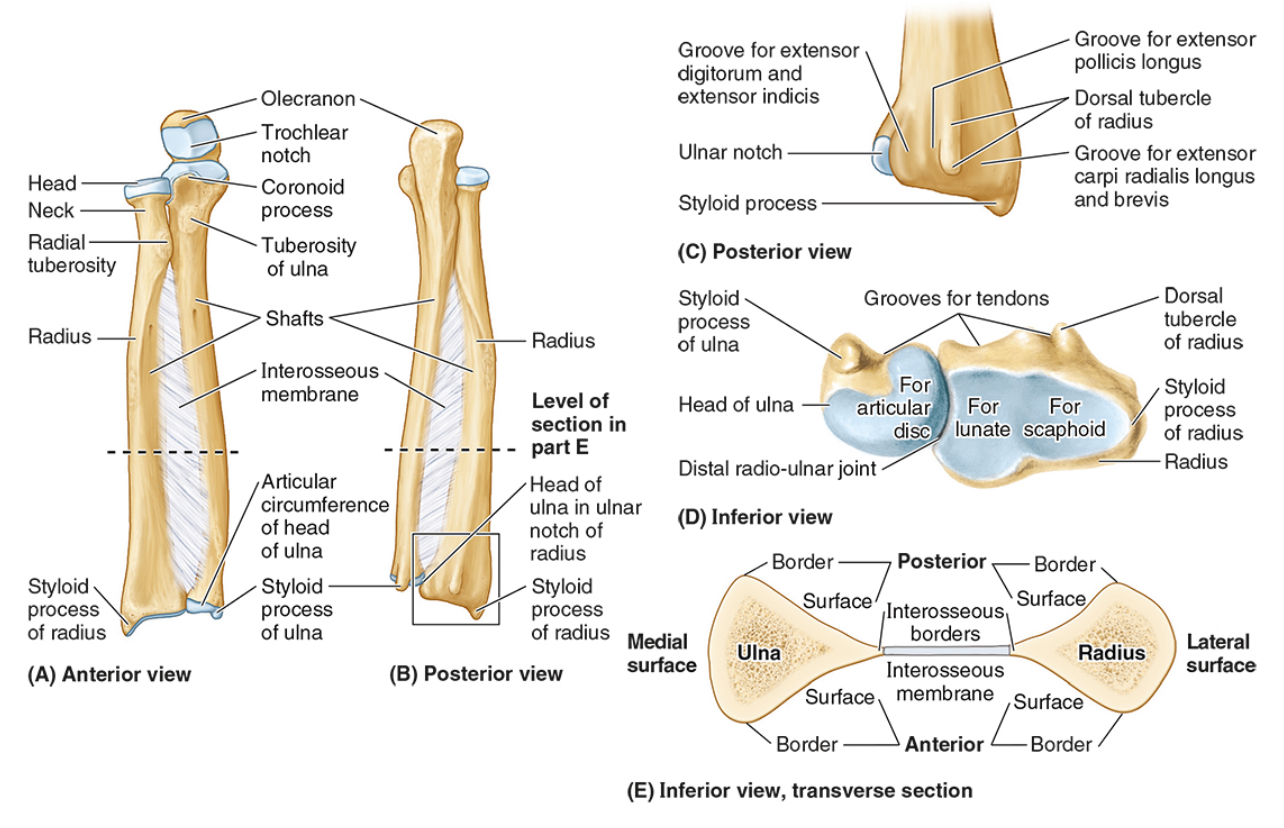

The ______ connects to the carpal bones of the hand at the wrist joint. The _____ widens distally to provide the proximal articular surface of the wrist (remember, the _____ is on thumb side of the wrist!)

(all the blanks are the same word)

Radius

The head of the radius

The neck of the radius

The radial tuberosity

The ulnar notch

The styloid process

The ____ is the medial forearm bone

Ulna

the olecranon (superior)

The coronoid processes (inferior)

The trochlear notch

The tuberosity of the ulna

The radial notch

The head of the ulna

Distal radio-ulnar joint